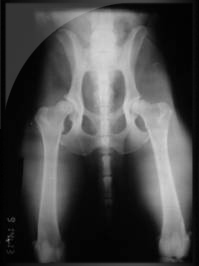

Otro detalle a considerar es la malformación de la cadera llamada Displasia. Por eso recomendamos adquirir un bulldog a criadores de esta raza, que se preocupan por dichas enfermedades que la mayoría son de origen genético. Con lo cual si se estudia el pedigree del perro con detención a la hora de cruce de líneas, es ciertamente seguro que se disminuye el riesgo de que los cachorros padezcan dicha malformación.

¿Que conocemos acerca de la displasia?

La displasia de cadera es una enfermedad biomecánica que se caracteriza por una incongruencia articular progresiva, provocada a partir de una laxitud articular y que finaliza en una enfermedad degenerativa articular (EDA).

La displasia coxofemoral (DCF) no es una enfermedad congénita, ya que las caderas son normales al nacimiento. La afección aparece a partir de un conjunto de factores ambientales Desde el punto de vista anatómico, la cadera es una articulación esferoide, formada por una cabeza redonda y una cavidad cotilo idea (el acetábulo), que ajustan perfectamente entre sí.

Actúan sobre una base genética múltiple, de alta heredabilidad (oscila entre 0,2 y 0,6 según la raza) que determina un retraso en la maduración de las estructuras de soporte articular que lleva, en mayor o menor medida, a la aparición de laxitud, primer paso hacia la incongruencia articular.